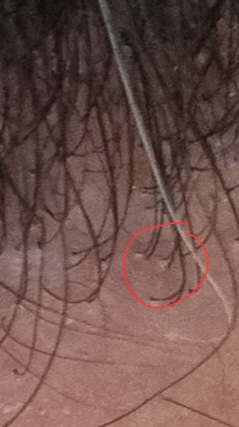

Εισαι σιγουρος οτι ειναι coblestoning? μου φαινεται δυσκολο εως απιθανο απο τον Bissanga, το να προεξεχει πολυ λιγο δερμα εκει που βγαινει η τριχα δεν νομιζω οτι ειναι coblestoning, το εχω δει σε παρα πολλα περιστατικα και εδω στο forum σε αποκαλυπτικες φωτογραφιες απο κοντα.

Ε τώρα μην μου πεις ότι κάτι τέτοιο είναι αναμενόμενο.

Μια ακόμη φωτο που φαίνεται λίγο πιο καθαρά

Από ότι έχω διαβάσει μια πιθανή αιτία εκτός τα οσα αναφερε ο jim είναι ότι τοποθετηθηκανε σε λεπτές οπές graft με μεγαλύτερη από όσο θα έπρεπε διάμετρο.

Τώρα αυτο διορθώνεται από δερματολόγο που πρέπει σιγά σιγά να αφαιρέσει τα εξογκώματα.